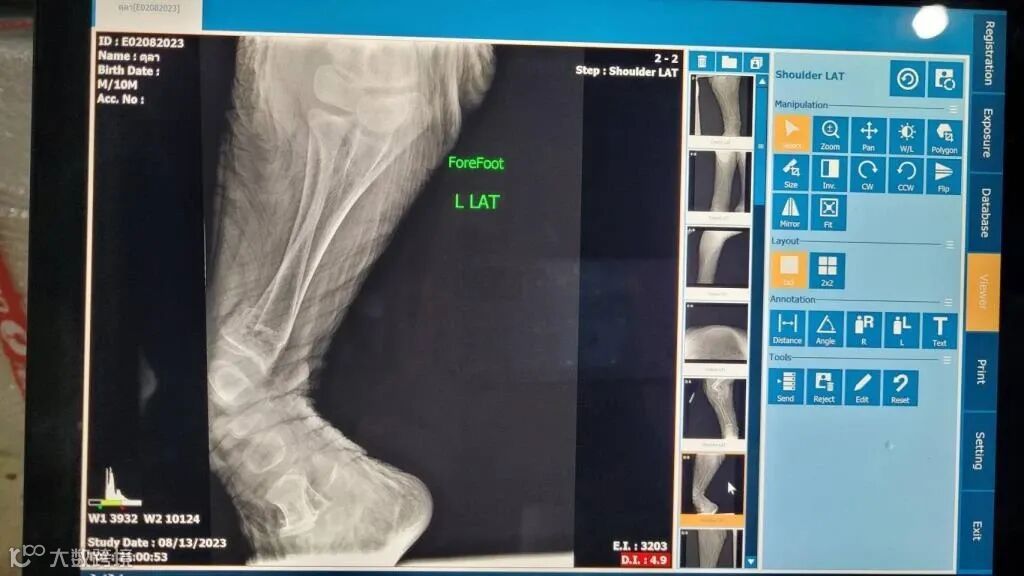

然而,命运似乎并不总是那么宽容。到了2023年7月底,图拉的双前腿不再像以前那样灵活,甚至开始出现肿胀。经过多次检查,被确诊为代谢性骨病。人们都陷入了巨大的痛苦,他们每天守在图拉的旁边,鼓励他,安慰他。尽管医生和所有的工作人员都做出了最大的努力,图拉还是在2023年8月13日的清晨离开了这个世界,他的鼻子紧紧地靠在饲养员的身边,那份信任和依赖,成为了最后的告别。